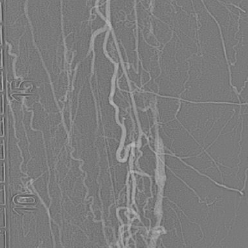

• Unique needle design / shape, axial protrusion or lateral protrusion selector, with excellent pushability and torqueability

• Highly stable support from a very low profile 4Fr catheter with a 0.018" catheter guidewire and 2.9Fr catheter with a 0.014" catheter guidewire

• Unique RO marker directly on the needle provides both radial and axial needle position information

• Unique catheter with the ability to advance laterally Inside hard plaque with its needle fully or partially deployed